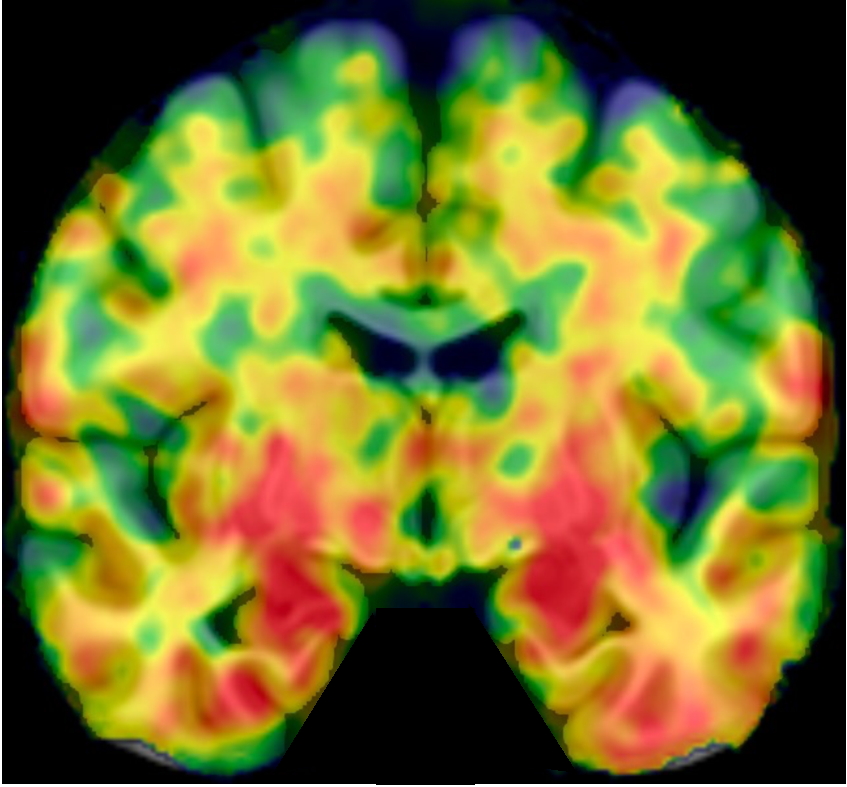

这需要结合核心2标志物——Tau蛋白。在临床上,医生会通过Tau-PET检查,观察Tau蛋白沉积在大脑哪个部位,从而确定疾病的病理分期:

【A期(初期)】

• 表现:核心1标志物阳性(Aβ比值降低),但Tau-PET检查阴性

• 意味着:大脑里已经开始产生毒性蛋白,但尚未造成明显损害

【B期(早期)】

• 表现:核心1阳性,Tau沉积出现在内侧颞叶

• 意味着:记忆中枢(海马体)开始受损